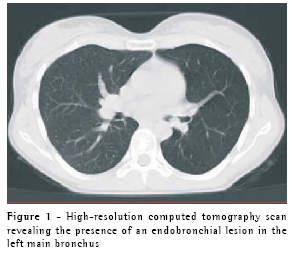

The subsequent high-resolution computer tomography scan revealed the presence of a circumscribed, pedunculated nodule projecting into the lumen of the left main bronchus, without involvement of adjacent mediastinal structures (Figure 1). Bronchoscopy revealed a vegetative lesion that was pedunculated and obstructive, measuring approximately 2 cm in diameter, in the left main bronchus (Figure 2). The patient was later submitted to a posterolateral thoracotomy for isolated resection of the affected bronchial segment, followed by surgical reconstruction of the bronchus. Histopathological examination of the resected segment revealed a lesion predominantly consisting of glandular structures and mucus-producing goblet cells, with no significant cytological atypia. The mitotic index was elevated, which is characteristic of a low-grade endobronchial mucoepidermoid carcinoma (Figure 3). Since being treated, the patient has been asymptomatic and has presented no evidence of recurrence, according to semi-annual monitoring with high-resolution computer tomography and bronchoscopy.

The chest X-ray is extremely important in all suspected cases of recurrent pneumonia since it allows the diagnostician to differentiate between recurrent and persistent pulmonary infiltrates. In many cases, the chest X-ray of a patient who is not currently infected may be normal, and a high-resolution computed tomography scan may help locate the endobronchial lesions.